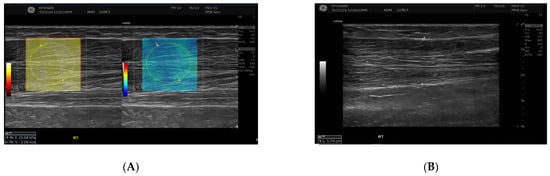

SWE measurements were acquired using a GE LOGIQ E10 (GE HealthCare, Chicago, IL, USA) system equipped with an ML 6-15 D linear transducer (frequency 6–15 MHz). Depth settings were standardized at 2.5–3.5 cm depending on muscle thickness. Each ROI was circular with a 5–7 mm diameter, placed centrally within the elastograms, avoiding fascia, vascular structures, and visible artefacts. Stiffness values were recorded in both kilopascals and metres/second, although statistical analyses were conducted using shear-wave velocity (m/s) for consistency. Frames with motion or colour dropout were discarded and reacquired. Muscle stiffness and thickness were evaluated in the biceps brachii and brachioradialis muscles, located proximal to the AVF site, Figure 1 and Figure 2. SWE imaging provided both Colour-coded elastograms and quantitative stiffness measurements (m/s; Figure 3). Participants were examined supine, with the shoulder in neutral rotation, the elbow extended to approximately 10–20°, and the forearm supinated. This minimized passive tension, which can influence shear-wave velocity. The transducer was positioned perpendicular to the muscle fibres, capturing measurements from the proximal, middle, and distal regions for comprehensive analysis. Measurements were taken before the haemodialysis to avoid intravascular volume shifts, with each parameter recorded three times and averaged for precision. Scans were performed by an experienced sonographer and verified by a radiologist, minimizing bias. A preliminary review of some patient records was conducted to refine data collection tools before the main data collection.

Figure 1.

This figure shows the Ultrasound assessment of stiffness near the arteriovenous fistula site (A) and brachioradialis muscle thickness (B). Shear wave elastography images (A) obtained at the fistula side demonstrate quantitative stiffness mapping within a defined region of interest, with stiffness expressed in velocity in metres per second (m/s). B-mode image (B) showing brachioradialis muscle thickness measurement at the contralateral (right) arm.

Figure 3.

This figure shows the comparison of brachioradialis muscle stiffness between the fistula and the contralateral arm. Shear wave elastography images showing stiffness measurements of the brachioradialis muscle. The left panel (fistula side) demonstrates a mean elasticity (velocity 2.13 m/s), while the contralateral arm (right panel) shows slightly higher stiffness (velocity 2.28 m/s). Measurements were taken in the mid-muscle belly using a high-frequency linear transducer, with Colour maps indicating relative stiffness (warmer colours represent higher stiffness).